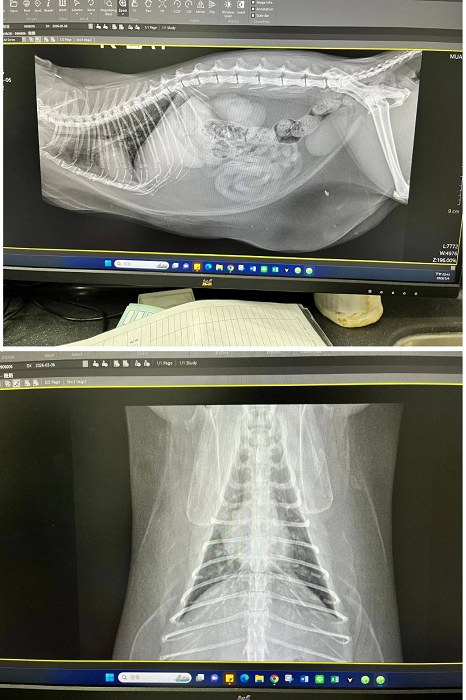

2026年3月初遷移回台北安養之家的妞妞,因照護員觀察到妞妞腹部腫大下垂,謹慎起見於是安排2026年3月6日於沐恩醫院進行看診,拍攝腹腔X光檢查,顯示胸腹部均為脂肪,屬於背部脂肪不太生成集中於腹部的體質,可不用擔心。X光看起來胰臟較大,不過質地沒有異常。同時針對胰臟較大進行超音波檢查,確認無異常。血檢也均正常。鎮靜後林院長幫妞妞修剪指甲及觸診,頭部有一側抓破皮,再請留意妞妞會不會時常抓癢。妞妞整體來說很健康,體重略重再觀察即可。本筆醫助是妞妞於2026年3月6日於沐恩醫院的醫療費用,包含看診、血檢、胸腔X光及超音波的費用。

1.妞妞檢查腹部下垂球狀。

2.拍攝腹腔X光片,顯示胸腹部均為脂肪,

屬於背部脂肪不太生成會集中於腹部的體質,可不用擔心。

X光看起來胰臟較大,不過質地沒有異常。

3.針對胰臟較大進行超音波檢查,確認無異常。

4.血檢均正常。

5.鎮靜後林院長幫妞妞修剪指甲及觸診,頭部有一側抓破皮,

再請留意妞妞會不會時常抓癢。

6.妞妞整體來說很健康,體重略重,再觀察即可。